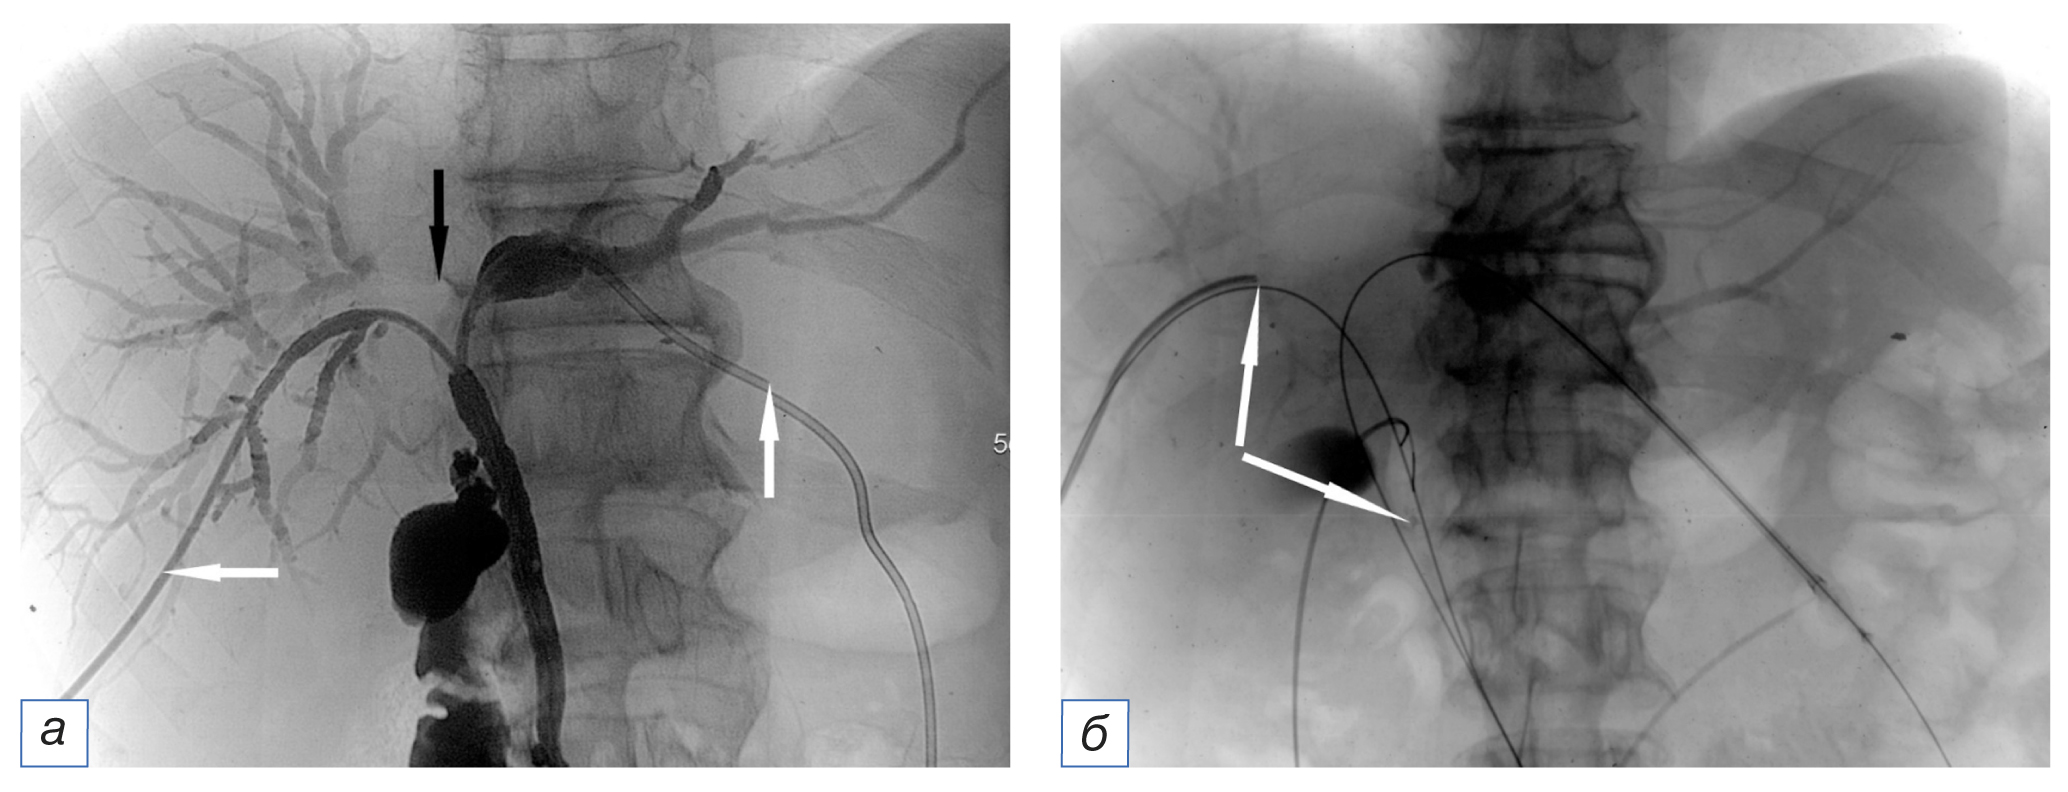

Диагностическую ангиографию выполняли по стандартной методике на столе дигитальных ангиографических комплексов Angiostar (Siemens, Германия) или Toshiba Infinix (Toshiba, Япония) через 2–4 сут после ФДТ. Осуществляли катетеризацию бедренной артерии по Сельдингеру и ангиографию гепатопанкреатобилиарной зоны с введением контрастного вещества автоматическим шприцем (рис. 2). Использовали современные висцеральные катетеры диаметром 4–5F и проводники различной степени жесткости.

Рис. 2. Ангиограммы того же пациента через 3 сут после фотодинамической терапии: а — целиакография катетером hook: определяется узурация ветвей левой печеночной артерии (белая стрелка), в проекции желчных протоков визуализируются два наружно-внутренних холангиодренажа (черная стрелка); б — возвратная портомезентерикография: сдавление опухолью ствола воротной вены (стрелка). / Fig. 2. Angiograms of the same patient 3 days after photodynamic therapy: а — common hepatic artery selective angiography with a “cobra” catheter (tumor invades branches of left hepatic artery — white arrow; two external-internal biliary drainages are seen — black arrow); б — late phase of superior mesenteric angiography (tumor compression of the portal vein — arrow).